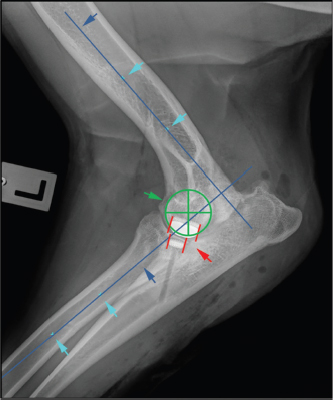

Cranio-caudal overlap of both implants was measured on ML views (Figs. 3 and 4).

First, the humeral longitudinal axis was drawn, as a line connecting the midpoints between both humeral cortices at 50% and distal 30% of its length. The radial longitudinal axis was determined by applying the same principle. A goniometer template was then positioned with each arm parallel to the respective longitudinal axis with the center of rotation at the center of the humeral condyle. Cranial and caudal edges of the implants were then marked on the template (Fig. 3). While the humeral arm of the template remained fixed, the radial arm with marked UImpl edges was first brought into full extension, positioning the ulnar implant caudal to the humeral one and then gradually flexed back to full flexion in order to mimic the full range of elbow motion. Extension angles for six elbow positions were recorded (Fig. 4):

Fig. 3. Determination of long bone axis as well as joint rotation center for measurement of cranio-caudal humero-ulnar implant overlap turquoise arrows: midpoints between cortices at 50% and 30% of the humeral and radial bone length; blue arrows: longitudinal bone axis of humerus and radius; green cross: center of elbow joint rotation, identical with center of humeral condyle; red lines: cranial and caudal edge of the humeral and ulnar implants.